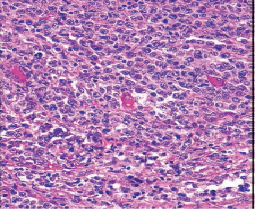

Morphology, the gold standard for any initial analysis—cytological analysis using a microscope to examine cells and histological analysis to examine tissues—is now complemented by a multidisciplinary approach: biological and genetic analysis according to WHO criteria. These costly techniques are not yet fully accessible to low- and middle-income countries, exacerbating inequalities in access to healthcare in these countries.

The latter is currently carried out by transmitting digitized microscopic images of interest (JPEG images) via the internet. These images are selected by local cytologists or anatomic pathologists using a microscope with a digital camera connected to a computer and a scientific exchange platform, the "i-Path" platform linked to the INCTR (International Network for Cancer Treatment and Research). This platform comprises several scientific exchange groups made up of identified doctors (hematologists, anatomic pathologists, clinicians) linked to a group of international experts in various fields of cancer. The latter comment on the images, helping local practitioners to make a diagnosis.

- Immunohistochemistry on sections.